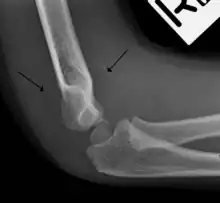

The fat pad sign, also known as the sail sign, is a potential finding on elbow radiography which suggests a fracture of one or more bones at the elbow. It is may indicate an occult fracture that is not directly visible. Its name derives from the fact that it has the shape of a spinnaker (sail).[1] It is caused by displacement of the fat pad around the elbow joint. Both anterior and posterior fat pad signs exist, and both can be found on the same X-ray.

The fat pad sign is invaluable in assessing for the presence of an intra-articular fracture of the elbow. An anterior fat pad is often normal. However a posterior fat pad seen on a lateral x-ray of the elbow is always abnormal. The patient will be unable to flex their elbow and requires orthopaedic input.[2]

The posterior fat pad is normally pressed in the olecranon fossa by the triceps tendon, and hence invisible on lateral radiograph of the elbow.[3] When there is a fracture of the distal humerus, or other pathology involving the elbow joint, inflammation develops around the synovial membrane forcing the fat pad out of its normal physiologic resting place. This is visible as the "posterior fat pad sign" and is often the only visible marker of a fracture, particularly in the pediatrics population.